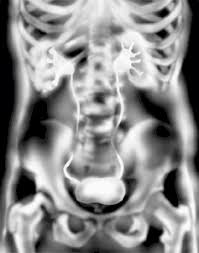

Do Kidney Stones Always Show On X Ray. Your radiologist will view the images and interpret the results. Ct scans use a combination of x rays and computer technology to create images of your urinary tract.

Not all stones are visible on abdominal x ray. Imaging tests can help tell your doctor how big it is and exactly where it s located. Results of a kub study may show injuries to your stomach or intestines.

Ct can identify tiny kidney stones and more importantly can determine whether there is obstruction. A plain x ray will only see kidney stones that have partially calcified. X ray results are usually available within a few minutes. All kinds of kidney stones show up on the ultrasound though.